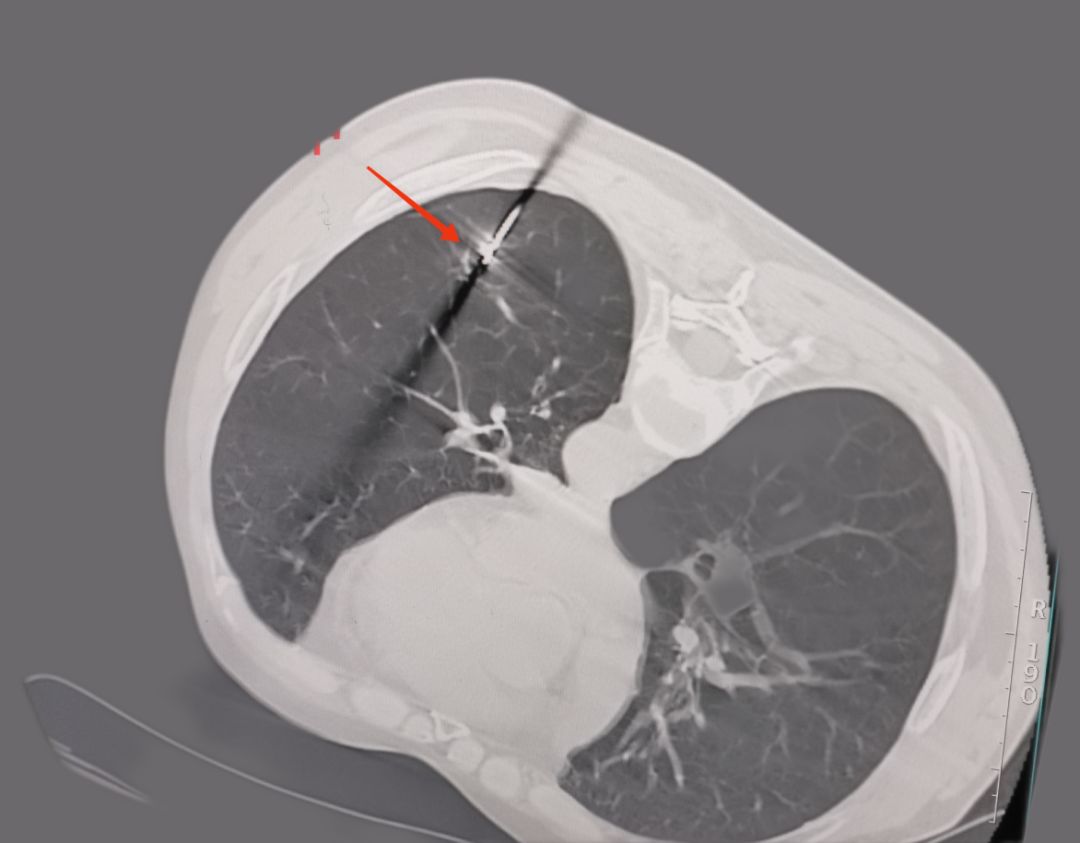

微波射頻消融手術(shù)中

微波射頻針精準(zhǔn)定位肺部結(jié)節(jié)

手術(shù)結(jié)束后,經(jīng)CT復(fù)檢確認(rèn),消融治療范圍完全覆蓋病灶,達(dá)到消融目標(biāo)?;颊呶锤胁贿m,在醫(yī)護(hù)人員的陪同下安全返回病房。